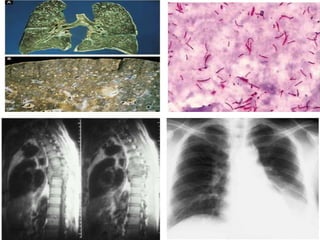

Momia Peruana de 700

años d.c.

Niño con TB Vertebral y

visceral, en la que se

observó BAAR.

Cultura Paracas.

Momia Peruana de 1000

Mujer que murió entre 40-

45 años de edad; con

lesiones pulmonares y

linfáticas, con evidencia de

DNA de M. tuberculosis en

Cultura Paracas. Museo de Ica - Perú   nódulo linfático.

1990. Cultura Chiribaya.